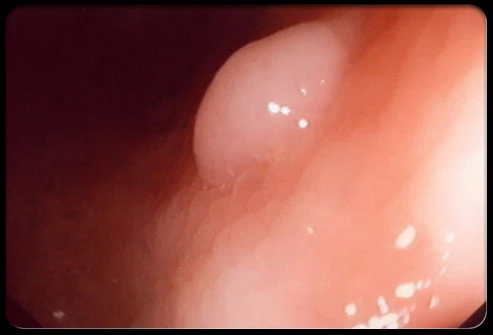

Bệnh ung thư đại trực tràng cũng rất hay gặp ở những người trẻ trong độ tuổi 20. Đây là bệnh gây tử vong đứng hàng thứ 4 sau các loại ung thư phổi, ung thư gan và ung thư dạ dày.

Hầu hết những người trẻ bị ung thư đại trực tràng thường do các polyp ung thư hóa hoặc gia đình có người có tiền sử mắc ung thư đại trực tràng.

Triệu chứng điển hình của bệnh là: đi ngoài ra máu, phân lỏng, phân nhầy như máu cá, đau bụng… kèm theo đó là cảm giác chán ăn, buồn nôn, giảm cân khi bệnh đã ở giai đoạn muộn.

Vì bệnh ung thư đại trực tràng dễ gặp ở những người tuổi đôi mươi, chính vì vậy mà đừng nên chủ quan với các triệu chứng bất thường trên cơ thể, hãy đến gặp bác sĩ để có được sự tư vấn và kiểm tra kịp thời.